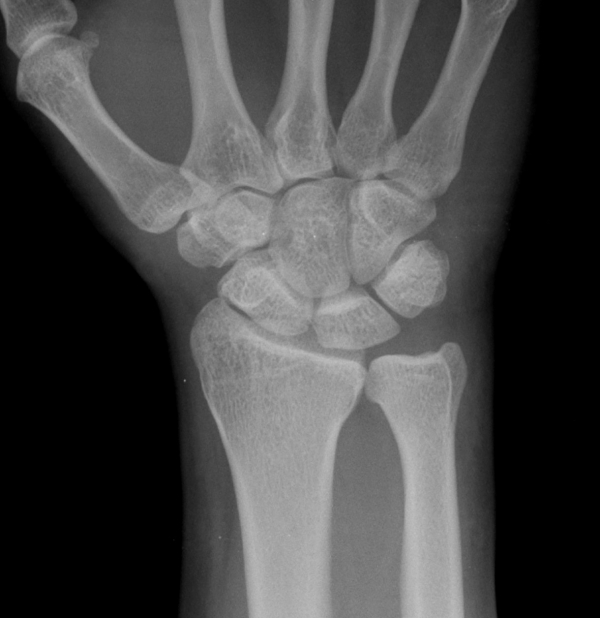

¹æ»ç¼± °Ë»ç : ƯÀÌ ¼Ò°ß ¾ø(»çÁø 5, 6).